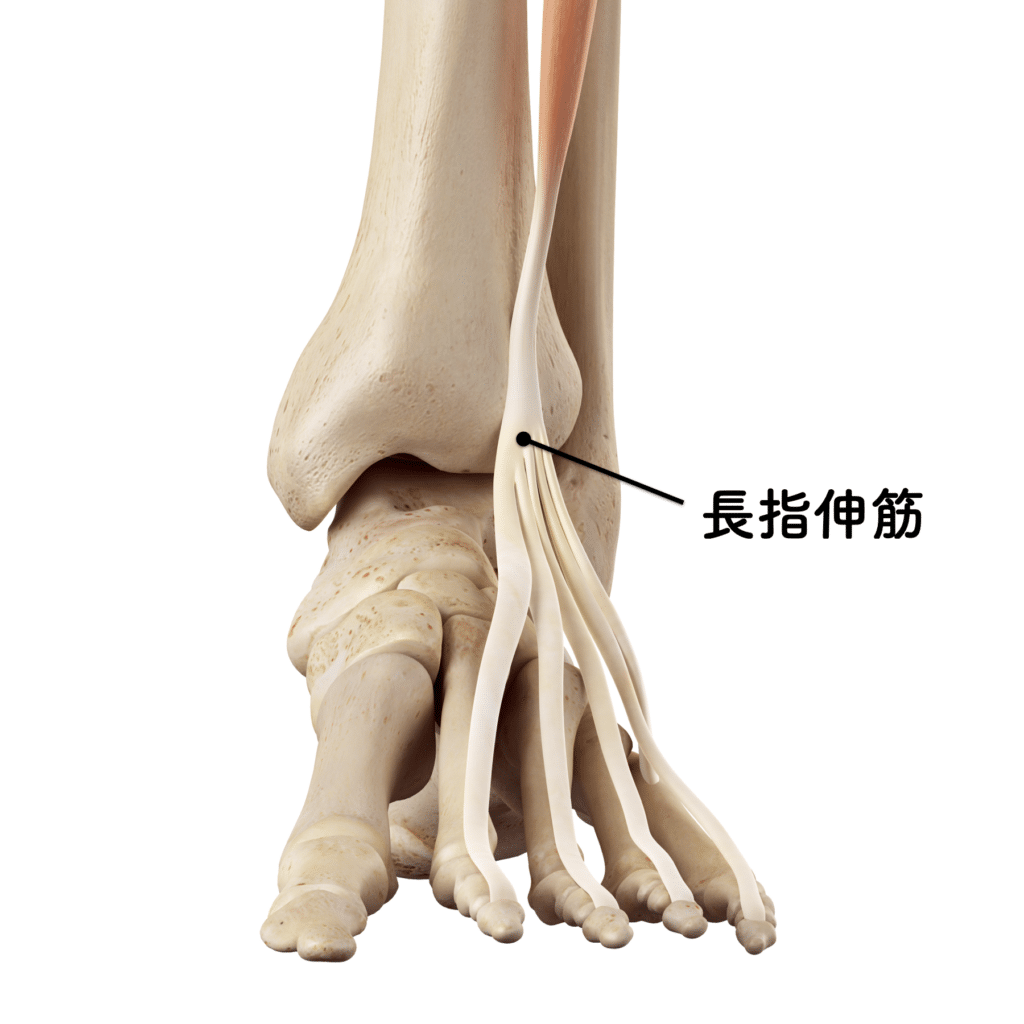

たとえば

・短趾伸筋

・長趾伸筋

の活動が低下すると、

対抗する屈筋群

・長趾屈筋

が優位になり、

筋力のアンバランスが生じます。

さらに、

このアンバランスが続くと、筋肉や腱の滑走軌道が乱れ、

小指を内側に引き込む力が強くなっていきます。